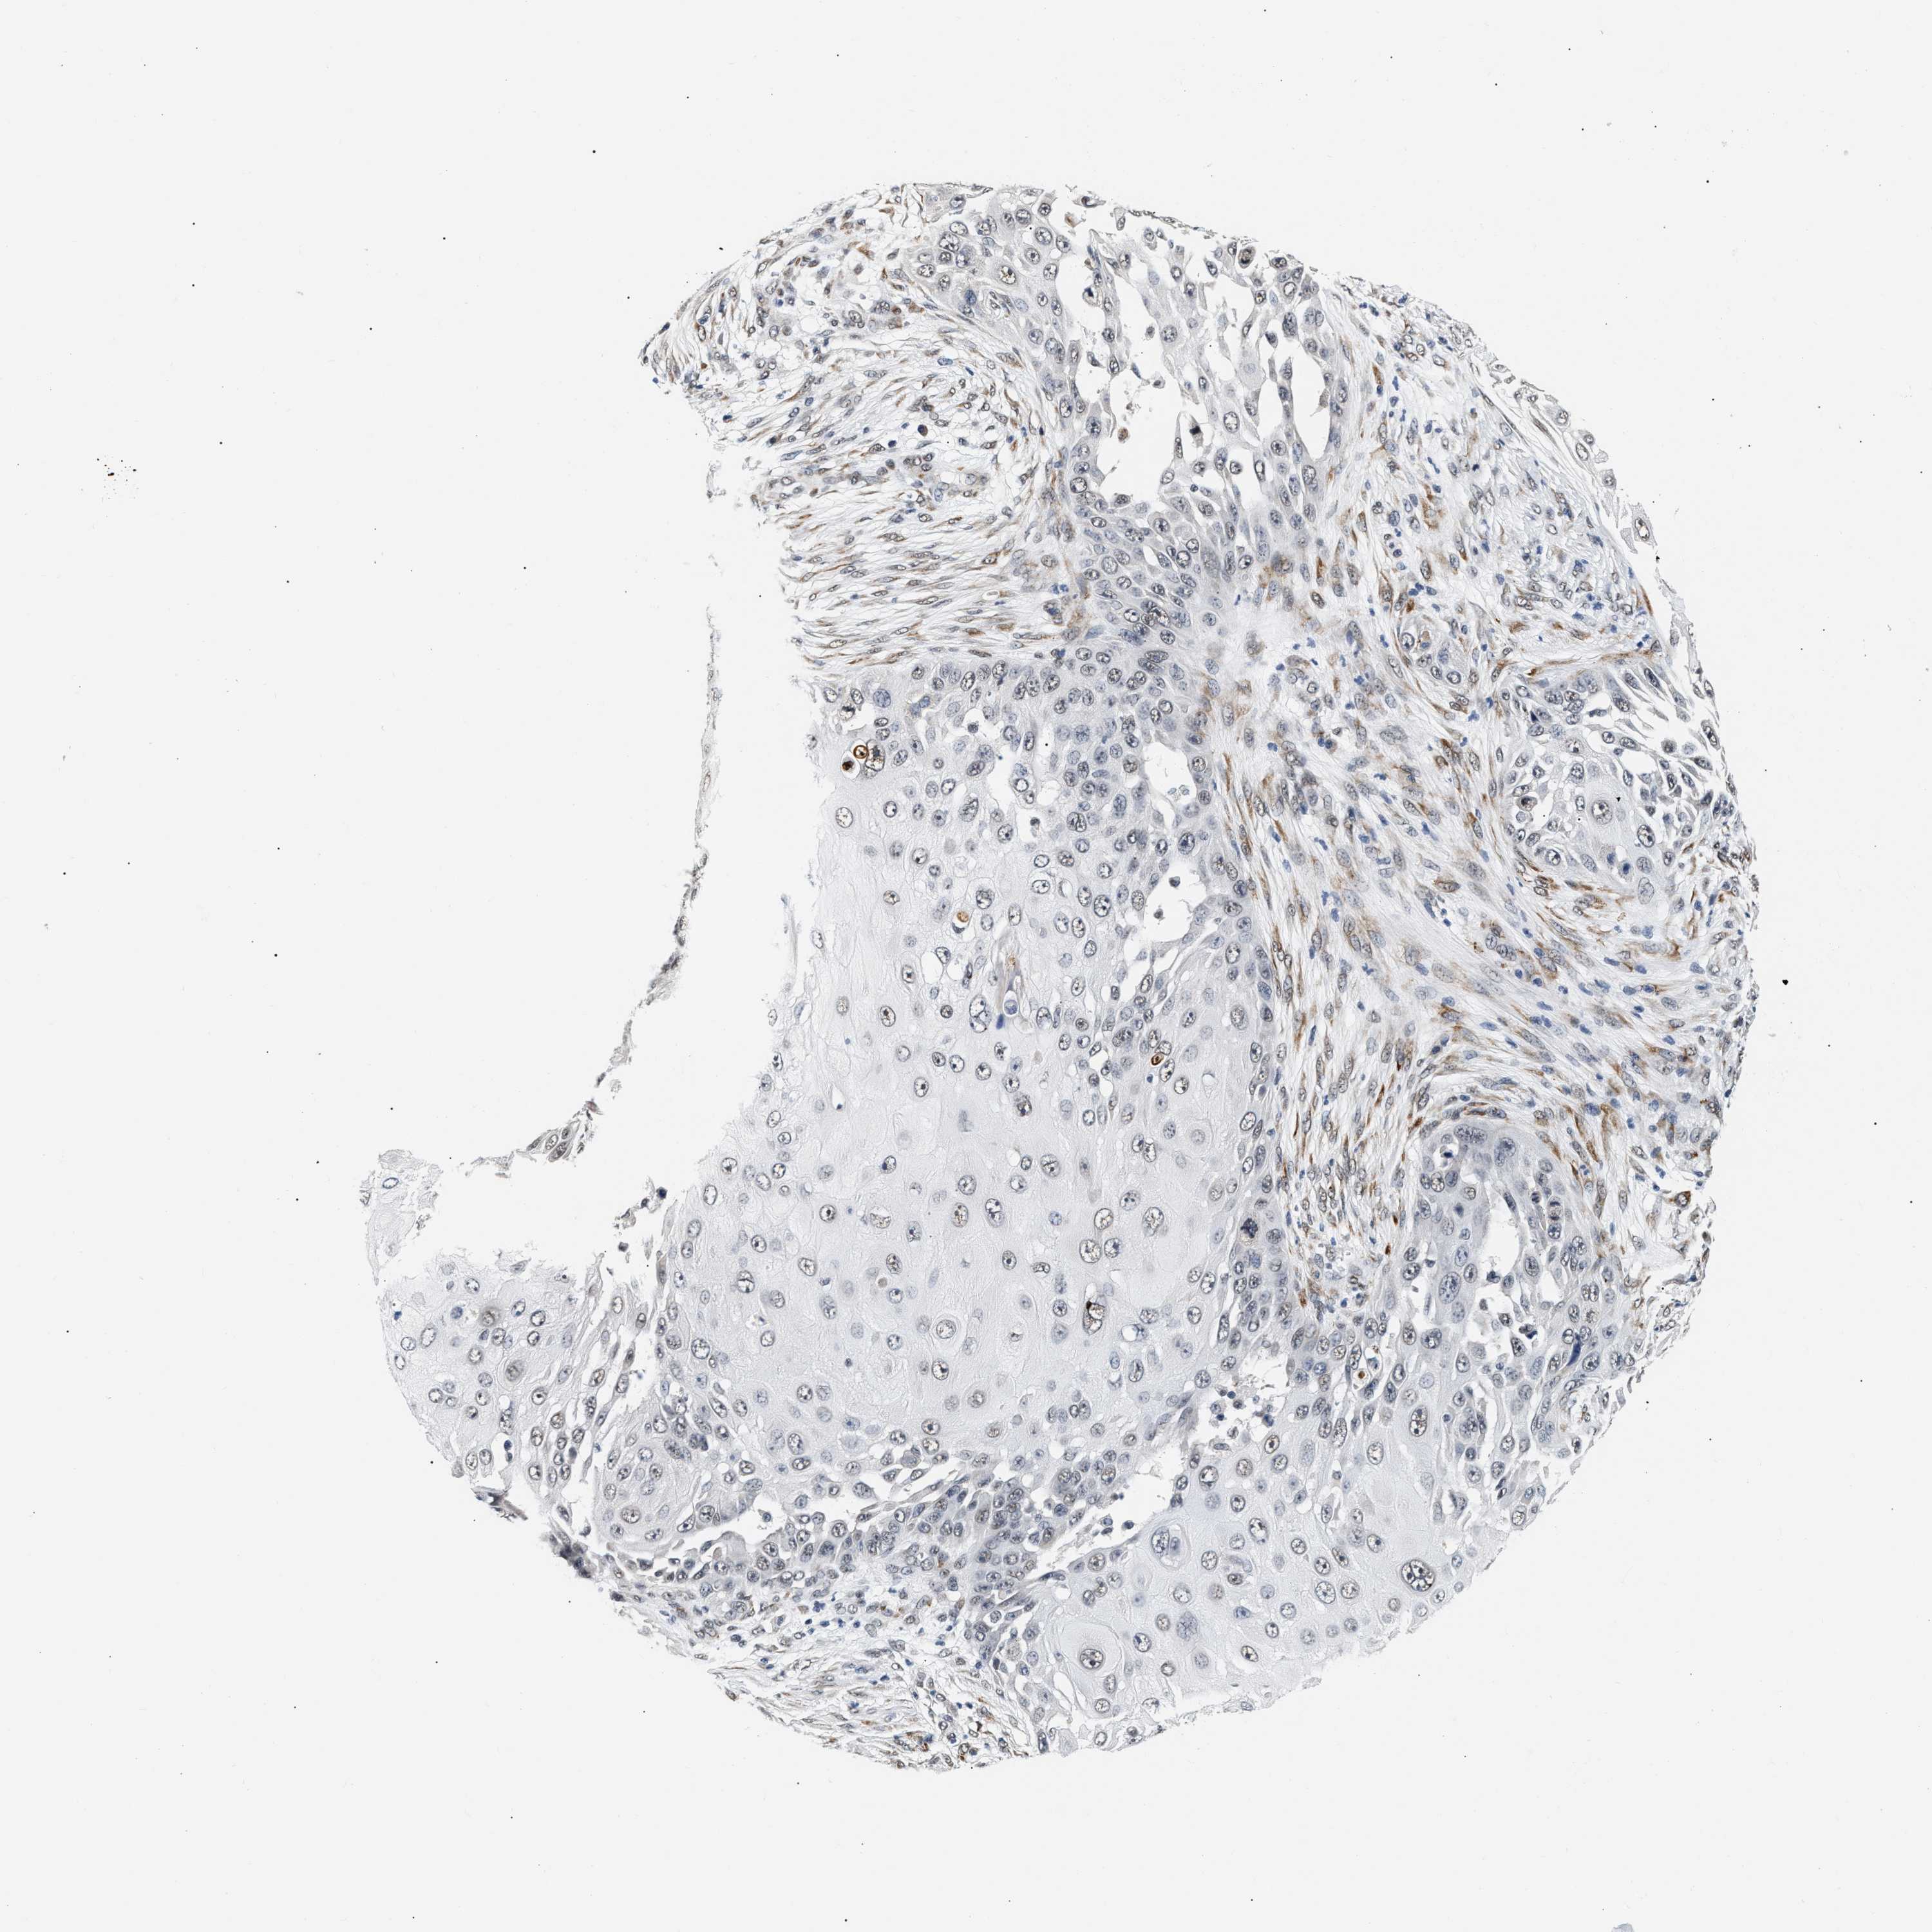

SKIN CANCER - Protein expressioni

A mouse-over function shows sample information and annotation data. Click on an image to view it in a full screen mode. Samples can be filtered based on level of antibody staining by selecting one or several of the following categories: high, medium, low and not detected. The assay and annotation is described here.

Antibody stainingi

Antibody staining in the annotated cell types in the current human tissue is reported as not detected, low, medium, or high, based on conventional immunohistochemistry profiling in selected tissues. This score is based on the combination of the staining intensity and fraction of stained cells.

Each image is clickable and will lead to virtual microscopy that enables deeper exploration of all samples and also displays staining intensity scores, fraction scores and subcellular localization as well as patient and tissue information for each sample.

Antibody HPA019096

Antibody HPA019687

Basal cell carcinoma

Squamous cell carcinoma, NOS

Squamous cell carcinoma, metastatic, NOS